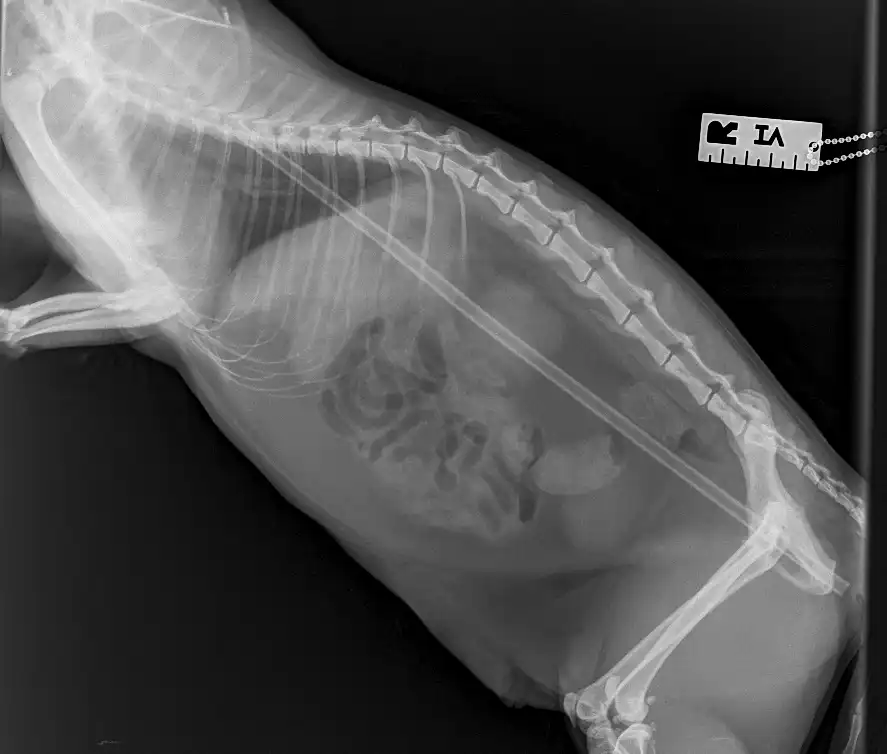

After vet Malwina Basinska discovered the seemingly superficial wounds were deeper than expected and felt something unusual under the cat’s skin, x-rays and an ultrasound revealed a 30cm-long stick-like object running the length of her body.

Mrs Tyrrell said: “We were all completely astonished when we discovered that the stick was in fact a plastic plant support, which had gone in near her groin, then pushed up through her ribcage and into her chest.

“Miraculously, it had missed all of Salvador’s vital organs, including her heart, lungs and liver.

“The surgery took a couple of hours as Malwina needed to work very carefully to remove the stick and had to cut it in half because of the plastic caps on each end.

“While these could have helped save Salvador’s life when she had the accident by helping the cane glide through her body and past her organs, they were stopping us pulling the stick back out through the ribs.”

The vet removed half the stick via Salvador’s abdomen and the other through her armpit.